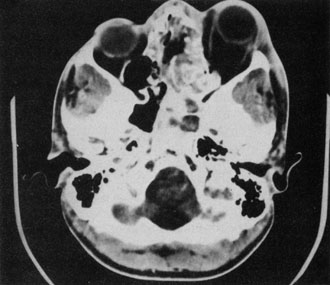

A subperiosteal abscess may rupture or invade the periorbit, resulting in an orbital abscess. This may or may not be contiguous with the subperiosteal collection on CT. There may be gas or air–fluid levels within the mass.51,56,58,59 An orbital abscess may present as an enhancing ringlike peripheral mass that can be either heterogeneous or homogeneous (Fig. 18).

Fig. 18. Orbital abscess. A. Computed tomography of an orbital abscess presenting as an enhancing intraconal mass on right side. B. T1-weighted image. C. T2-weighted image. Note area of high signal corresponding to abscess.